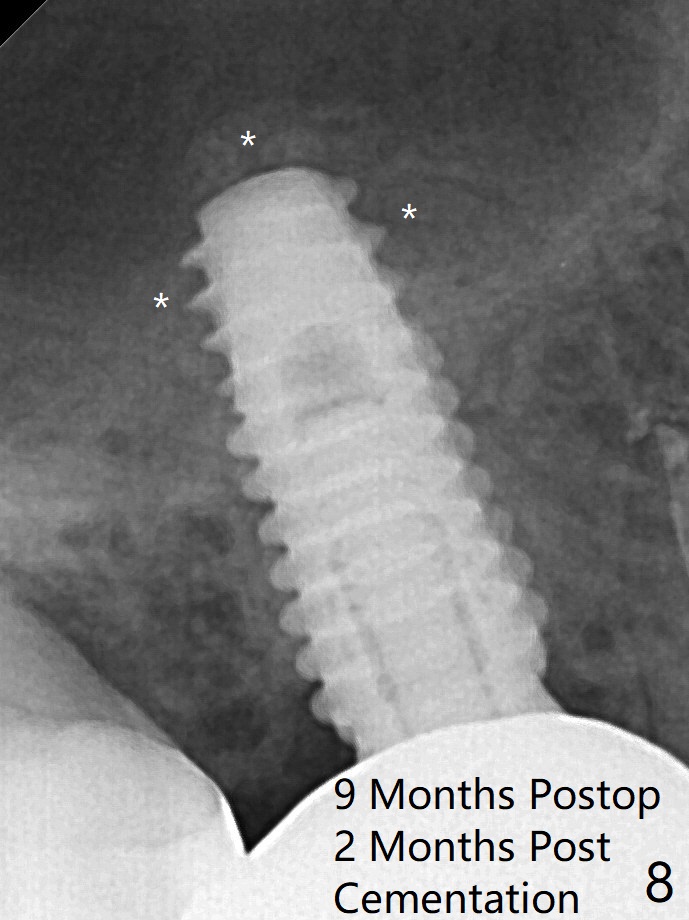

There is apparent mature bone in the sinus 9 months postop (Fig.8 *).